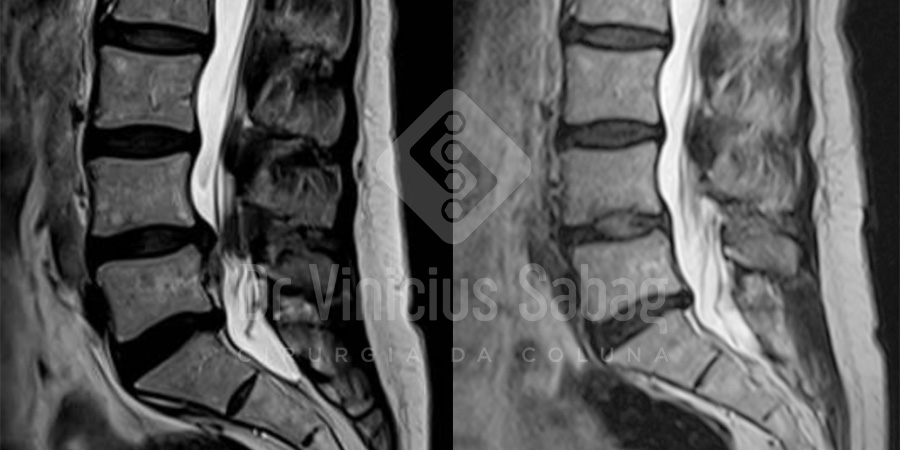

Ressonância magnética evidenciando a presença da hérnia discal lombar migrada inferior associada a estenose do canal lombar no nível L4-L5.

Foi realizada ressonância magnética de controle no pós-operatório, a qual demonstrou descompressão completa do canal lombar e retirada total da hérnia discal, exatamente conforme o planejamento pré-operatório.

Ressonâncias pré (esquerda) e pós (direita) operatória evidenciando a retirada completa da hérnia e descompressão dos nervos.